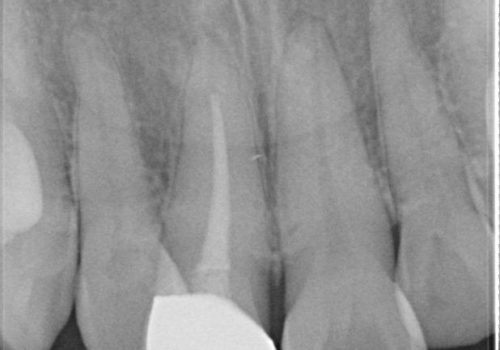

- 右上の前歯が左隣の歯に比べて色が暗いのが気になるとのことで来院されました。

右上1は根管治療がされており、神経がないため歯自体も変色していること、詰め物の色も変色していることをふまえ、オールセラミッククラウン(スペシャル)による治療を行うことになりました。

根尖に病変はないこと、患者さんが根管治療は希望されなかったため、土台のやりかえからかぶせものまでを行っております。